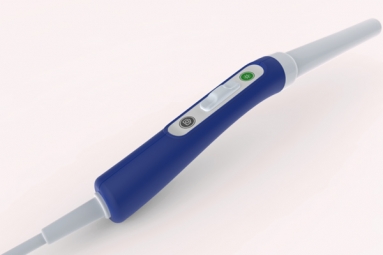

Read MoreIndian-American Scientist Builds Inexpensive Tool to Spot Cervical Cancer December 21, 2018 09:32

An Indian-American Professor of Global Health and Director of Global Women's Health Technologies at Duke University, Dr. Nimmi Ramanujam, has developed a low-cost diagnostic device called the 'Pocket Colposcope' to detect cervical cancer. According to…